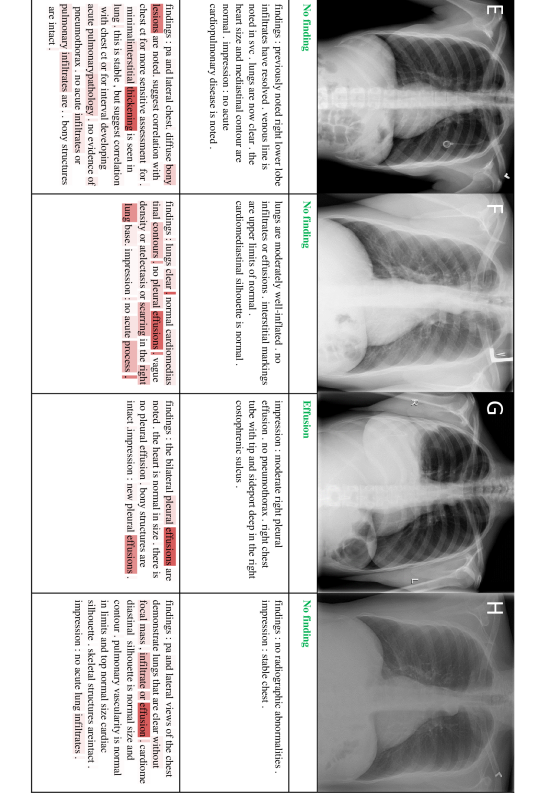

In this section, we present 20 more classification and reporting results (case E-X) from the proposed TieNet in addition to the four examples (case A-D) shown in the main paper. Sample images are illustrated along with associated classification Predictions (P), original and generated reports. Text attentions are highlighted with different saturation levels over the generated text. Darker red means higher weights of the text attention. Correct classification predications are marked in green, false predictions in red and missed predictions in blue.

Figure 5: 4 sample image Classification Predictions (P) along with original and generated reports. Text attentions are highlighted over the generated text. Correct predication is marked in green, false prediction in red and missing prediction in blue.

Refer to caption

Figure 6: 4 sample image Classification Predictions (P) along with original and generated reports. Text attentions are highlighted over the generated text. Correct predication is marked in green, false prediction in red and missing prediction in blue.